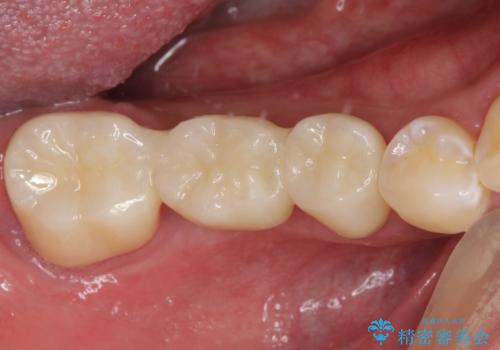

- ブリッジの歯のないところにインプラントを入れて、銀歯を白くやり替えたいと来院された患者様です。

歯の欠損している箇所にはインプラント治療をし、銀歯と仮詰めの部分はセラミックインレーにて補綴することとしました。

すべての治療の前に親知らずの抜歯も行っています。